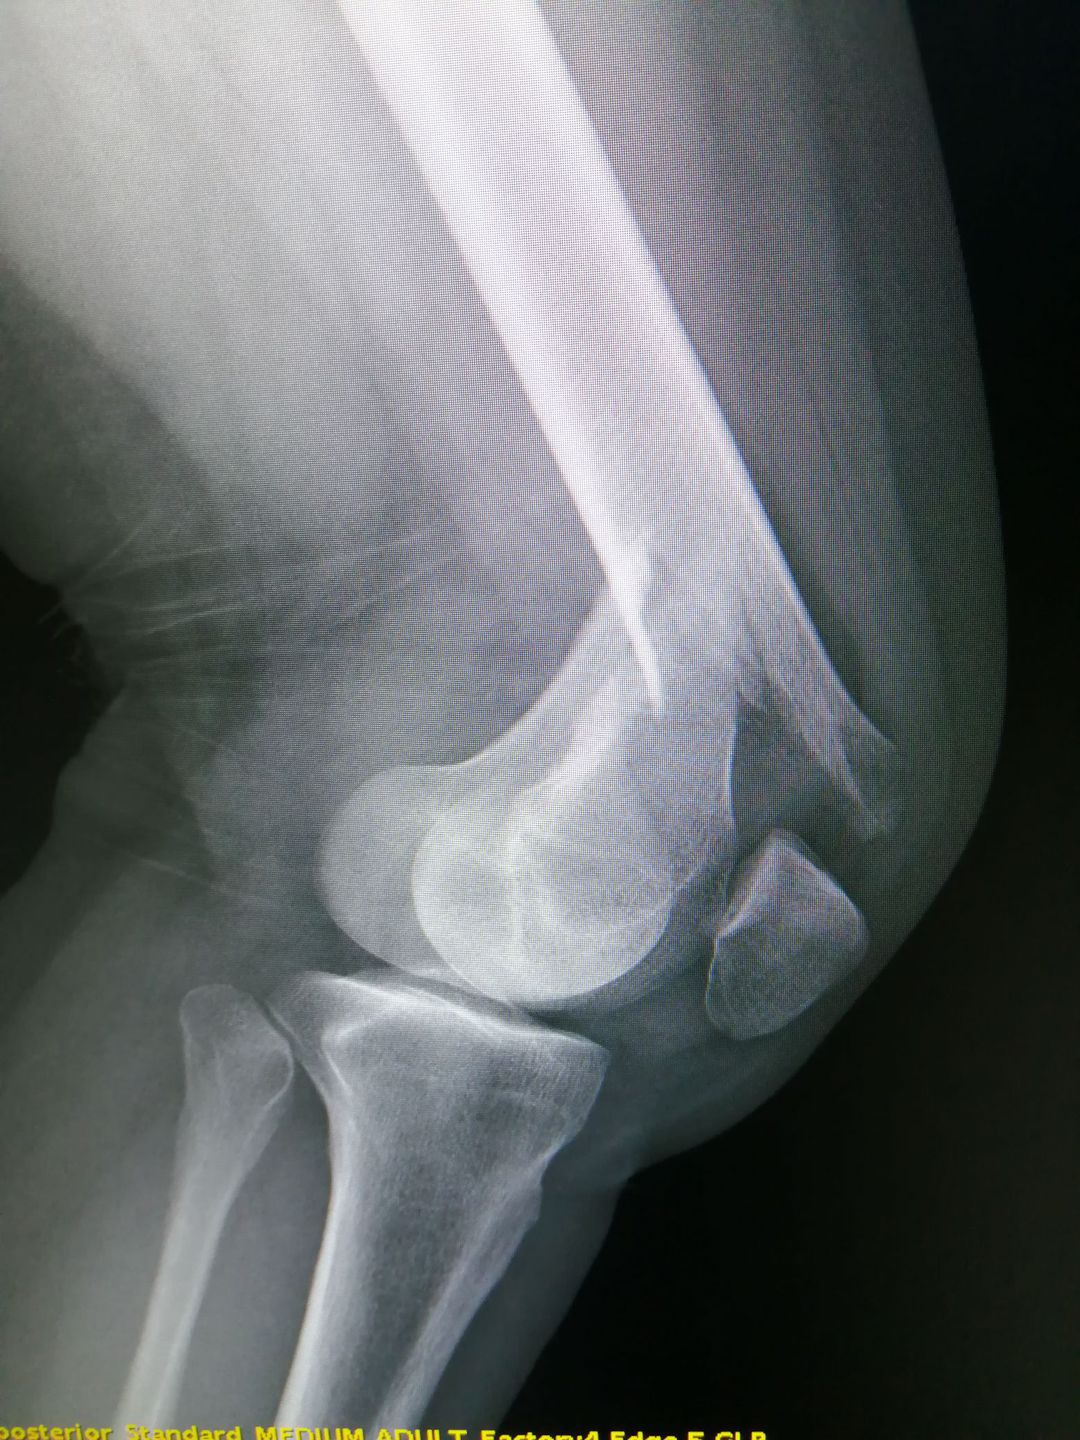

Distal femoral fractures

Left knee lateral view

Trauma

Xray

Knee

Femur